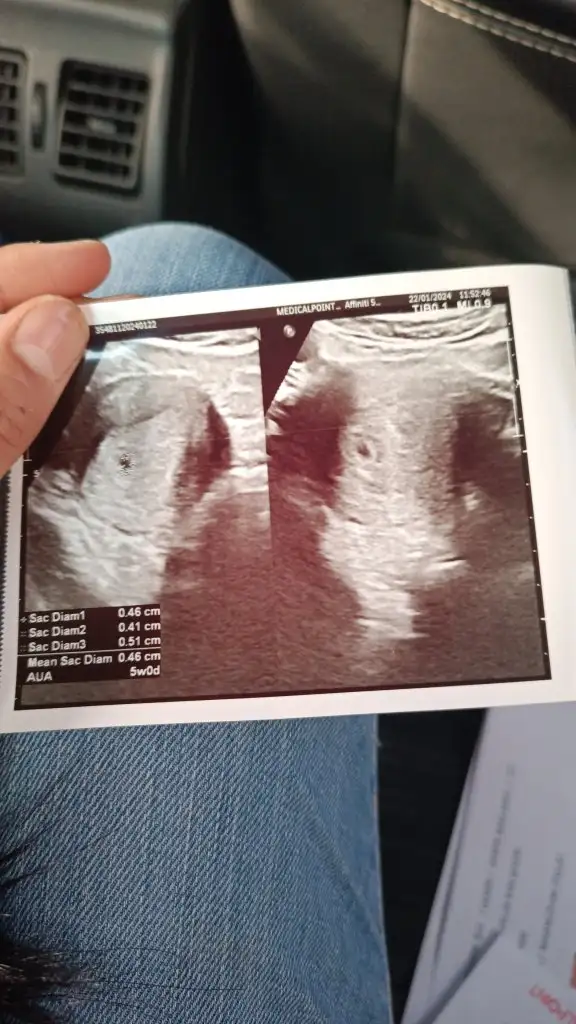

Bilmiyorum neden aldılar. Kese gözüküyor, büyümüş hatta. Ama yolk kesesi ise bebek gözükmedi mesela. Ah bi anlasam. Mahfoldum sabahtan beri

Eklentiler

• IMG-20240122-WA0001.webp

IMG-20240122-WA0001.webp

47,5 KB · Görüntüleme: 72